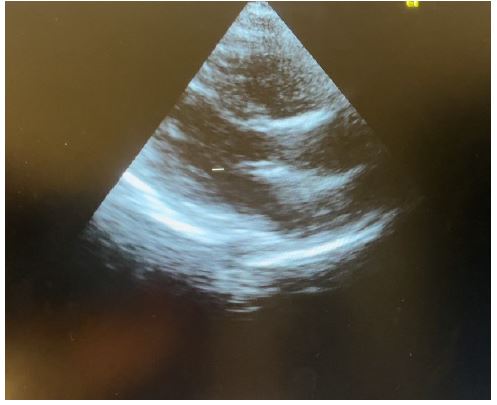

Presenting a 50-year-old immunosuppressed patient who was referred to our hospital for management of massive pre-tamponade pericardial effusion in respiratory distress. Patient was received in the emergency department and an emergency cardiac echography was done which confirmed the referral diagnosis of massive pre-tamponade pericardial effusion with massive bilateral pleural effusions. Patient was immediately prepared and taken for subxiphoid surgical drainage.

Transthoracic echocardiography is the best diagnostic imaging, useful in diagnosis and management of tuberculous pericardial effusion. Echocardiography can provide an estimate of the size of effusions. Generally, the size of the effusion on echocardiography indicates the volume of pericardial fluid as follows: small (<10 mm), which corresponds to 50-100 mL pericardial fluid; moderate (10-20 mm), corresponding to 100 - 500 mL pericardial fluid and large (>20 mm), corresponding to >500 mL pericardial fluid [19] . The study of Diakité et al. showed 18% of moderate abundance and 81% of high abundance among 49 cases of tuberculous pericarditis [6].